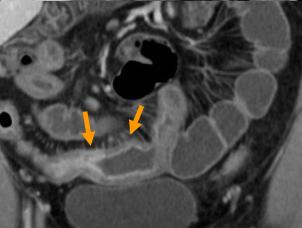

Signe de peigne " comb

sign " ( fleche jaune ) et epaissisement de la paroi

de ileon . Maladie de Crohn en phase aigue . Image

TDM . |